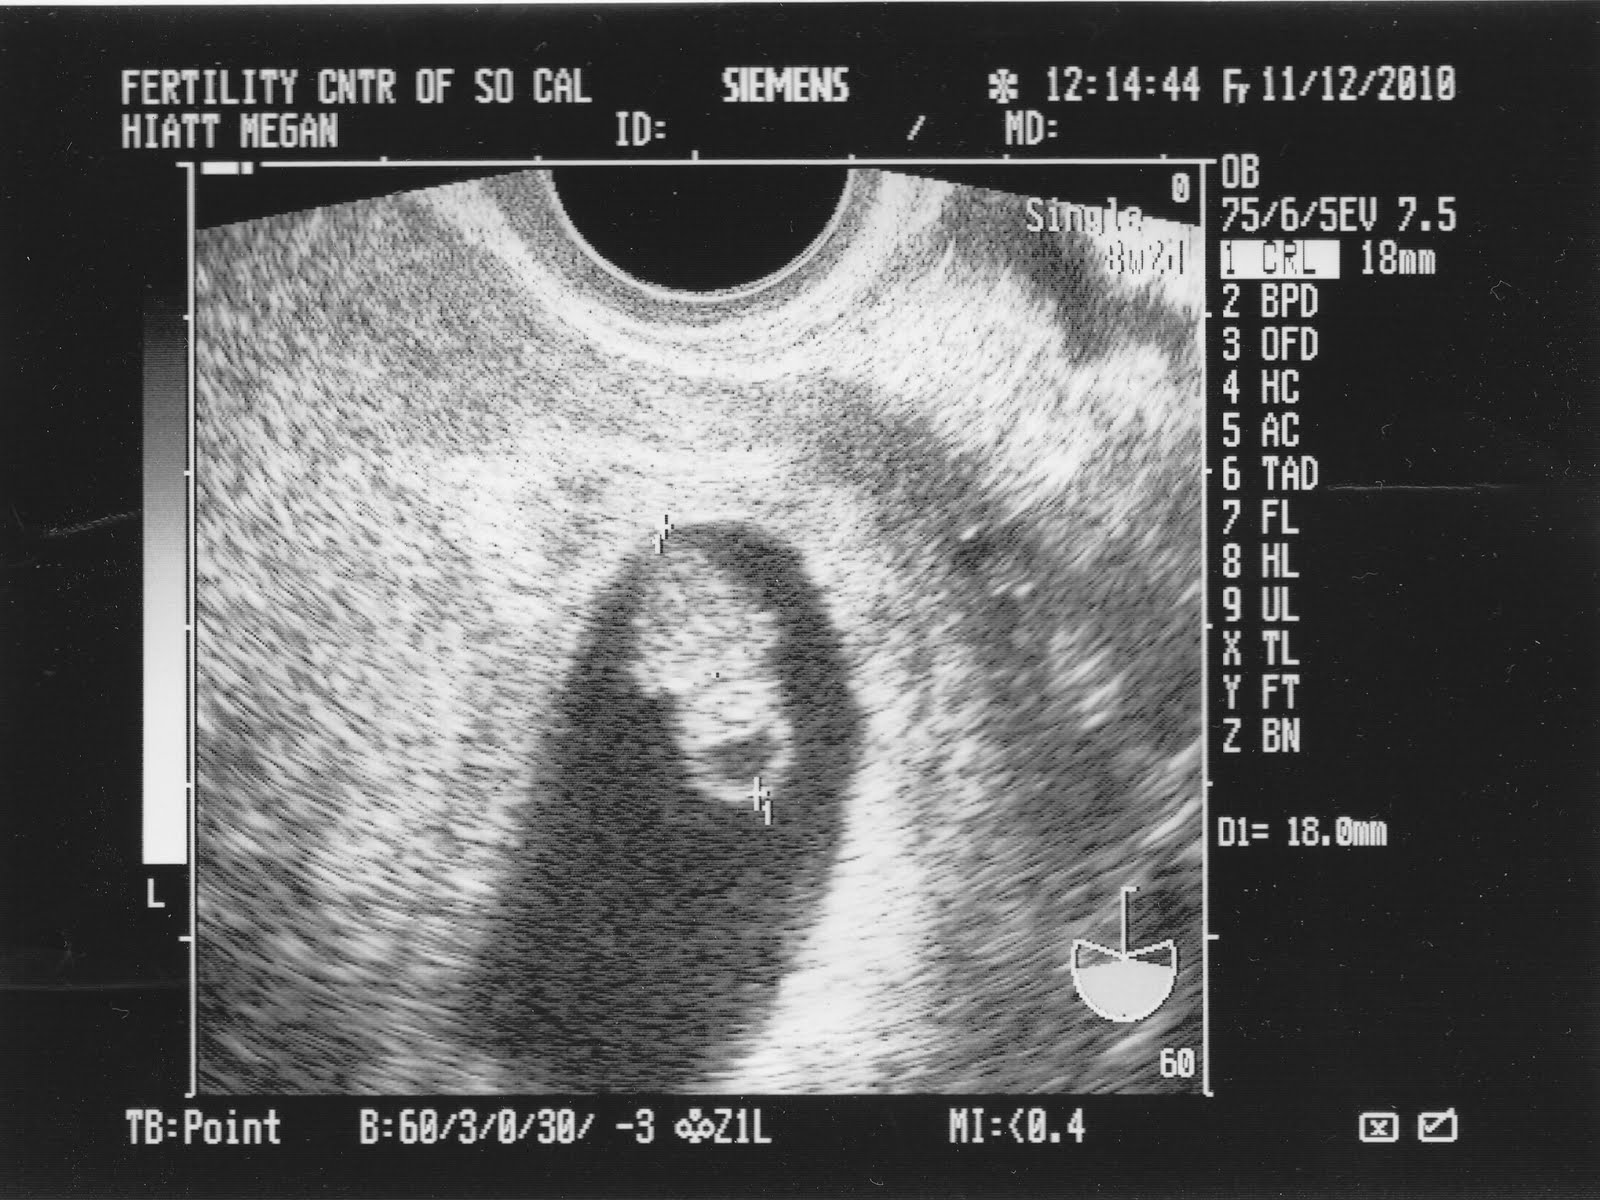

Ультразвуковое исследование (УЗИ) является одним из наиболее распространенных методов диагностики в медицине. Во время УЗИ врач использует специальный аппарат, называемый ультразвуковым сканером, чтобы создать изображение внутренних органов и тканей пациента.

Для получения фото УЗИ пациенту обычно предлагается лечь на специальный стол в позиции, наиболее удобной для проведения исследования. Врач наносит гель на кожу в области, которую необходимо исследовать, и затем прокатывает ультразвуковую головку по поверхности кожи. Ультразвуковые волны проникают внутрь органов и тканей, отражаются от них и возвращаются обратно к ультразвуковой головке, где преобразуются в изображение на экране.

Фото УЗИ могут быть черно-белыми или цветными, в зависимости от настроек ультразвукового сканера. Они могут быть сохранены в цифровом формате для последующего анализа и диагностики.